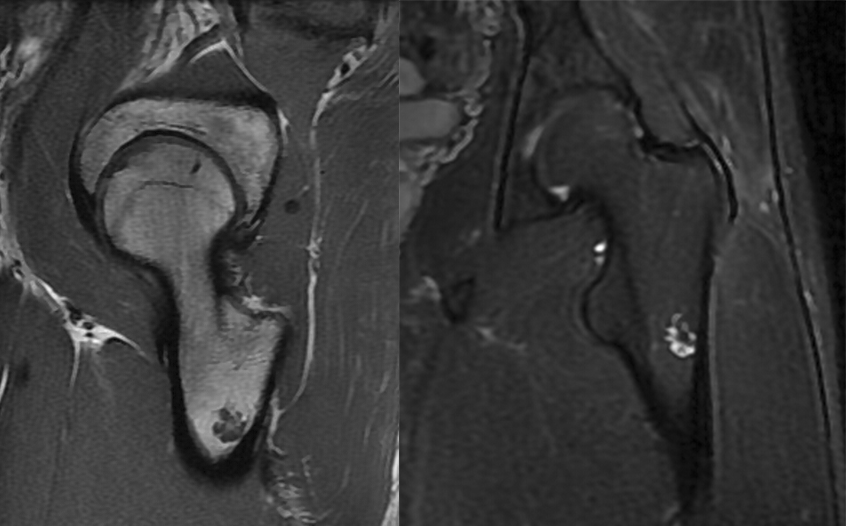

肿瘤对骨骺板和关节软骨的破坏是对骨破坏的继续。缺乏血管的骨骺板对恶性肿瘤有抵抗作用,骨骺板可暂时阻止肿瘤的蔓延,但当肿瘤进一步发展时, 骨骺板亦可被破坏,X 线平片或 CT 可表现为先期钙化带密度减低、中断或消失。MRI 可显示肿瘤从干骺端跨越骨骺板侵犯骨骺(图 15、图 16)。肿瘤突破关节软骨向关节腔发展时, 可表现为关节面破坏、塌陷(图 17), 关节腔内出现软组织肿块。少数良性骨肿瘤如软骨母细胞瘤, 亦可超越骺板向两侧发展或突入关节腔内, 此为肿瘤膨胀生长所致, 而非浸润性破坏。

图 15.骨骺板破坏:骨肉瘤

图 16.骨骺板破坏:骨肉瘤

图 17.关节软骨破坏:骨肉瘤